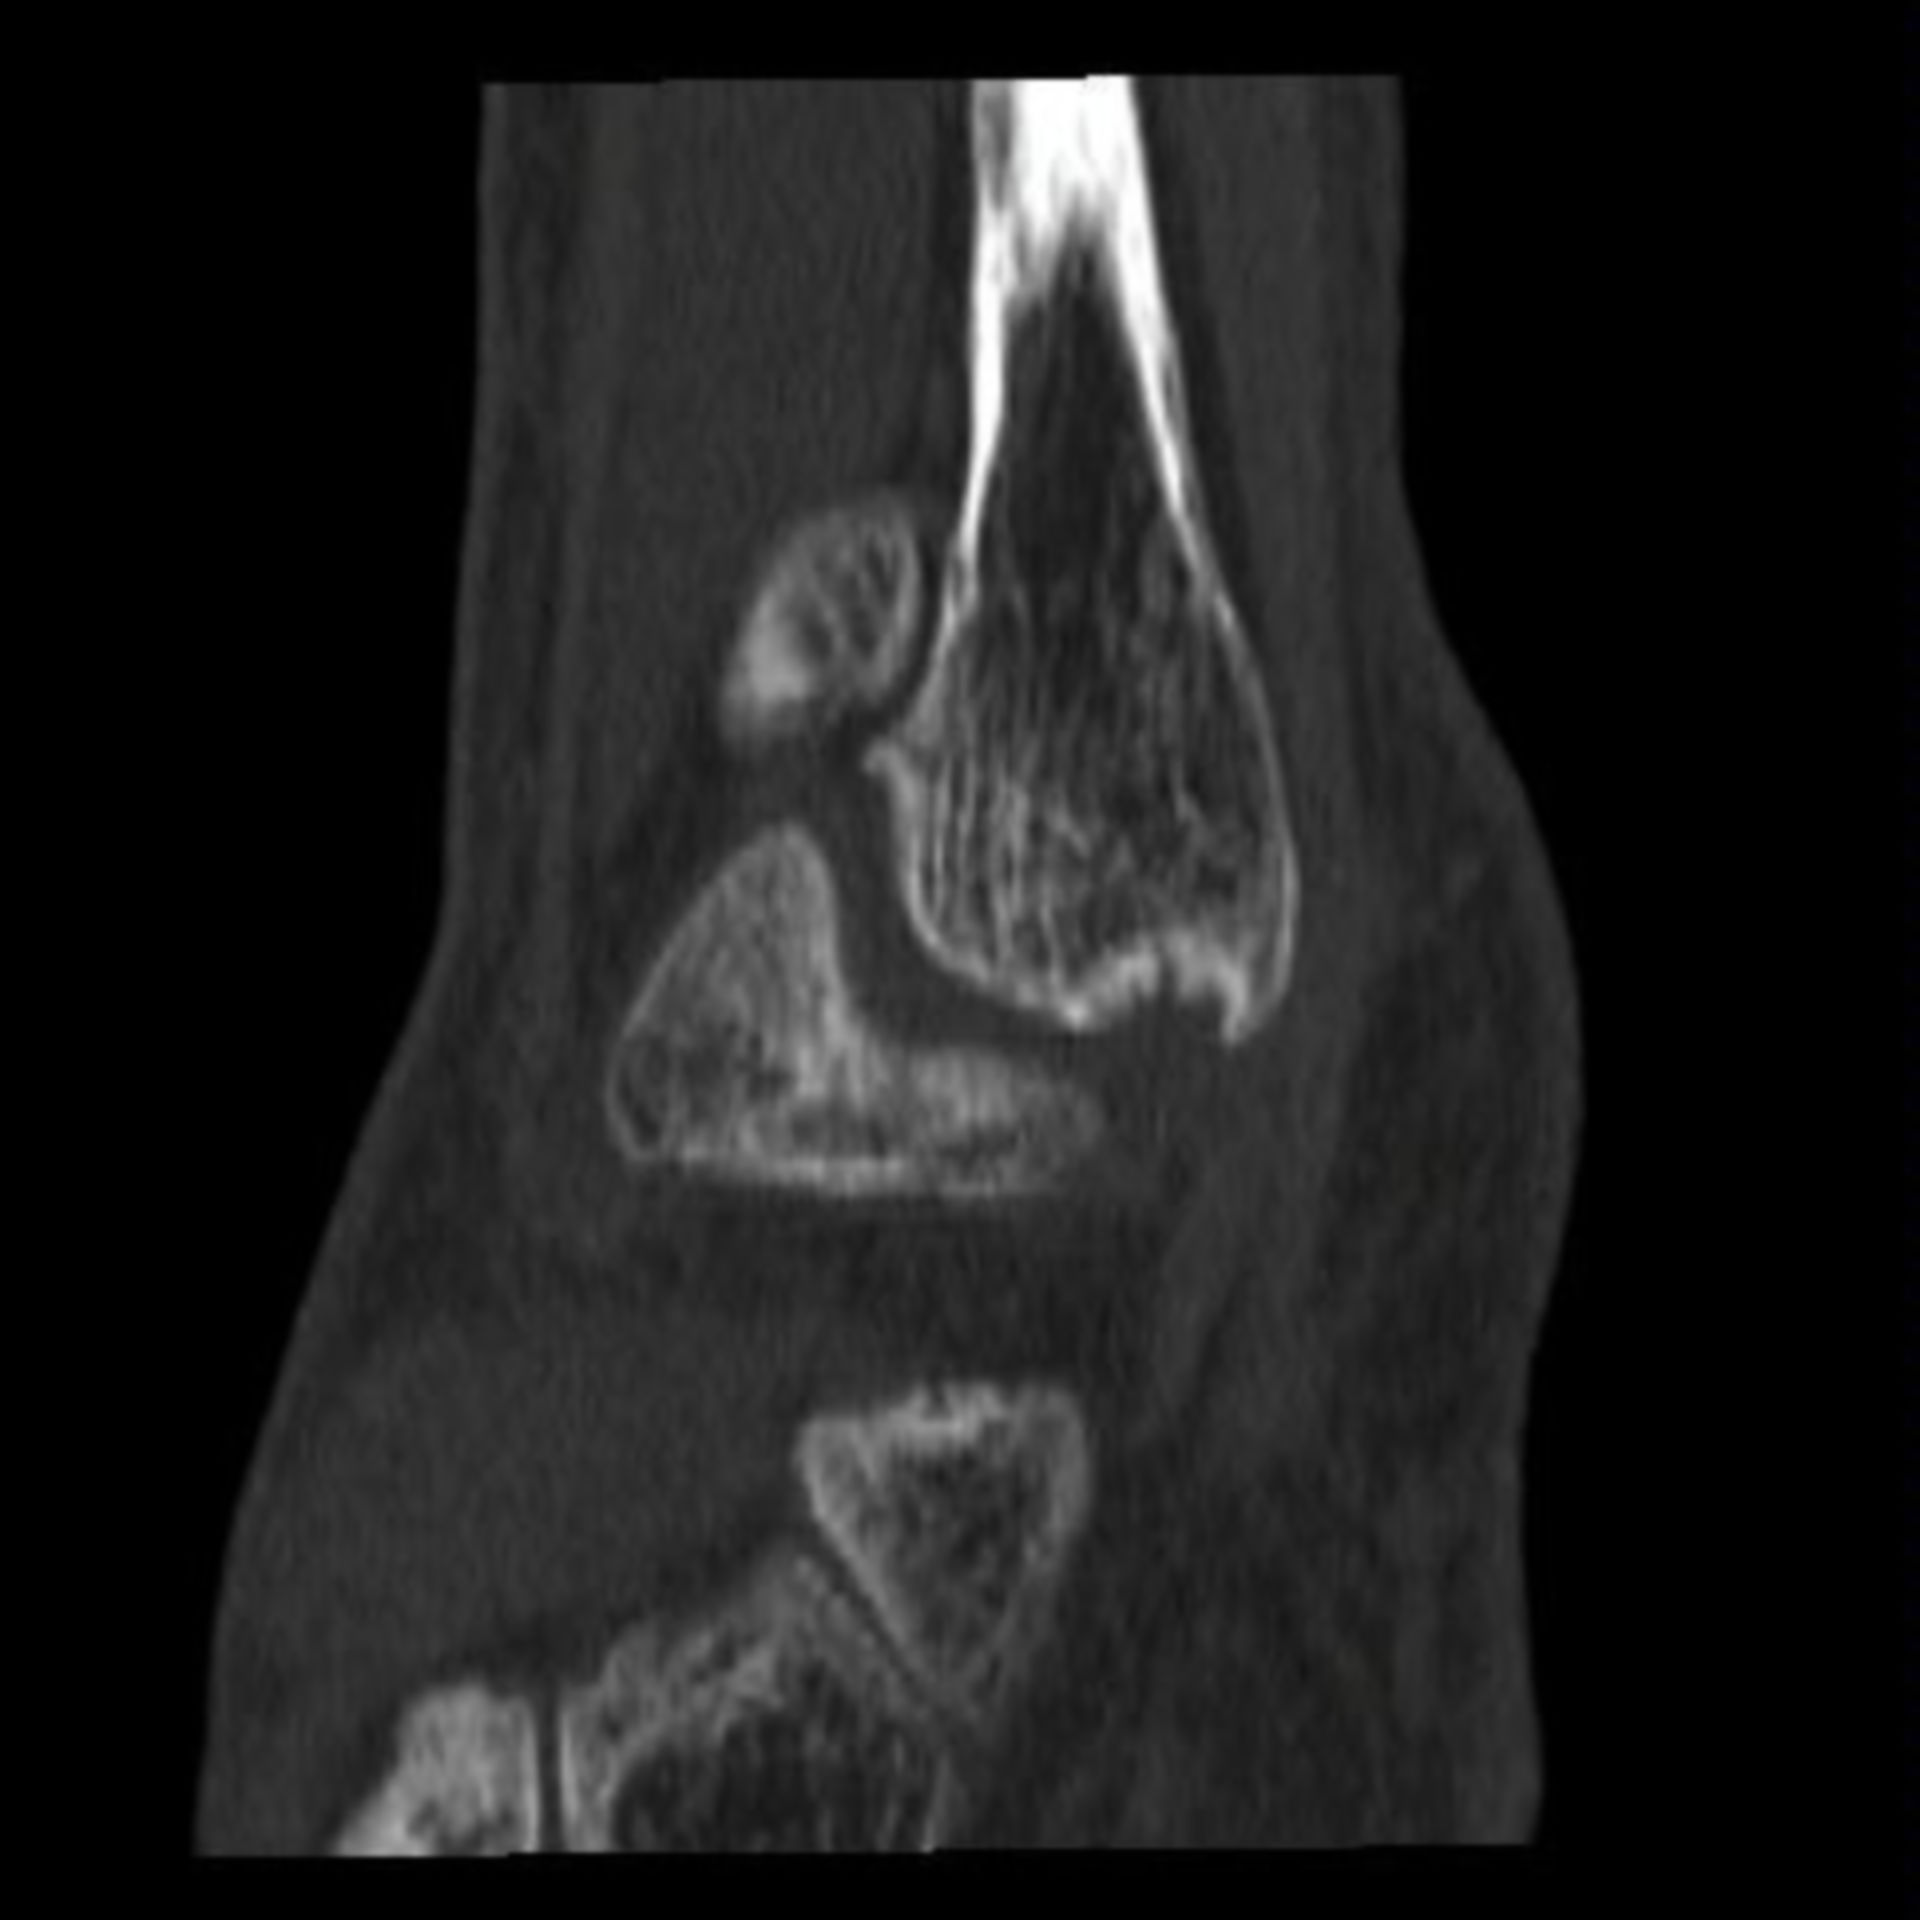

MRT Knie – DocCheck MRT Niere3 – DocCheck

MRT: Knie – DocCheck MRT in der Krebsmedizin

MRT Knie links HWS ARTHROSE, MRT Stockfotografie – Alamy

MRT Knie links MRT der akuten MS Stockfotografie – Alamy

MRT Knie links Mrt Bilder Schulter Sehnenriss – Captions Blog

MRT: Knie – DocCheck MRT Schädel – DocCheck

MRT: Knie – DocCheck MRT Knie links

MRT Knie linksสถานีMRTแทบแตก? คนเยอะมาก รถไฟไทย🇹🇭พามาดูความลึกความยาวสถานีสามยอดไทยสร้างได้ไง!ความลึกเท่าตึก3ชั้น😯